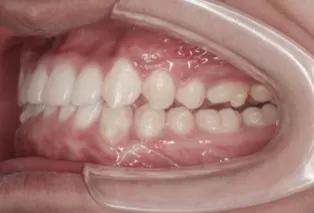

Photos intra-orales